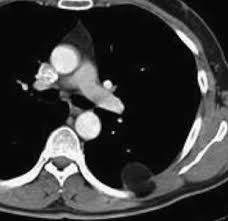

ct scanning not reliable for correct diagnosis of pleural mesothelioma, says new study. A short summary of this paper. This lets the doctor compare areas of higher radioactivity on the pet. pleural effusion occurred in 74% of those patients. pleural mesothelioma affects up to 40,000 people worldwide, 1 yet with around 2000 annually in the united states, it is considered a rare cancer. One study showed pleural thickening was evident in 94% of pleural mesothelioma patients who underwent a ct scan. Although the chest film findings of pleural mesothelioma are well described, there are few descriptions of the findings of computed tomography (ct). More common than mesothelioma occurring in the abdomen. A biopsy is the only definitive way to confirm a mesothelioma diagnosis. Some machines can do both a pet and ct scan at the same time. Comparison of ct and mr imaging. Although it is less effective at detecting peritoneal (abdominal) mesothelioma, ct scans are still the most useful imaging study for diagnosing peritoneal mesothelioma. 37 full pdfs related to this paper.

ct is the first imaging technique used for diagnosis, staging, and assessment of therapy response.

pleural mesothelioma can cause fluid to build up around the lungs in the chest (called a pleural effusion). The 2016 mesothelioma audit data reported that in the uk in 2014 pleural mesothelioma accounted for 2179 cases (97%), with 70 peritoneal cases (approximately 3%).1 in 2007, the british thoracic society (bts) statement on mesothelioma was published in response to a request from the About 75 percent of all mesothelioma cases diagnosed each year are pleural mesothelioma. It is the least advanced stage. pleural mesothelioma commonly presents with dyspnea. ct is particularly valuable in assessing the extent of malignant mesothelioma as well as establishing the presence of pleural effusion or parenchymal disease obscured by a pleural effusion. Doctors also use mesothelioma blood tests to measure treatment response. Although, ct has intrinsic limitations due to low soft tissue contrast and the current staging system as well as criteria for evaluating response, it does not consider the complex growth pattern of this tumor. Pleura) and chest wall (the "parietal" Unlike other malignant mesotheliomas that occur in the abdomen, heart, or testicles, this form of mesothelioma is a cancer that occurs in the pleura, or the tissue lining of the chest cavity that encloses the lungs. Computed tomography features in malignant pleural mesothelioma and other commonly seen pleural diseases. Staging of malignant pleural mesothelioma: The investigators anticipate that the intrapleural of the vaccine strain measles virus will enable the virus to specifically infect and kill cancer cells and.